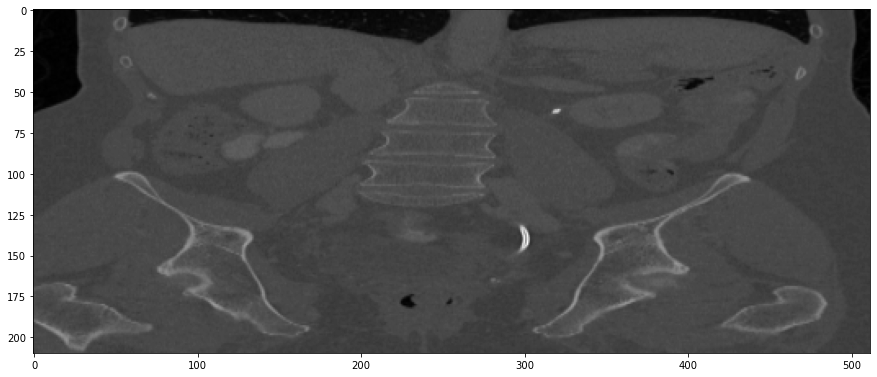

Refer to caption

Figure 1: Examples of lesions in liver, lung and lymph nodes on 1.25, 2.5 and 5 mm slice interval images adopt from [31]. The left panel shows a close-up of (a) liver metastasis on a 1.25 mm slice interval image, (b) lung lesion on a 2.5 mm image, and (c) lymph node metastasis on a 5 mm image. The right panel shows the computer-aided contour, 2 maximal perpendicular diameters and three-dimensional views of each lesion on (from left to right, respectively) 1.25, 2.5 and 5 mm slice intervals.

Multi-slice helical CT has been extensively utilized as a non-intrusive imaging technique since then and has proven especially valuable in the examination of lung diseases like lung cancer [8, 9, 10], Chronic Obstructive Pulmonary Disease (COPD) [11, 12, 13], and Idiopathic Pulmonary Fibrosis (IPF) [14, 15, 16]. Moreover, the application of CT scans is not restricted to pulmonary investigations alone; it is greatly employed to examine other anatomical regions, including the head-neck [17, 18, 19], heart [20, 21, 22], kidney [23, 24, 25], and liver [26, 27, 28]. CT has indeed become the preferred method in medical practice for imaging and identifying these conditions, thanks to its remarkable sensitivity and specificity. The effective execution of a lung disease screening protocol is deeply contingent upon the precise identification and evaluation of biomarkers, including pulmonary nodules, thickening of the airway walls, and traction bronchiectasis. However, such elusive radiomics features (RF) are highly affected by he acquisition thickness of CT images shown in Figure 1. Previous research showed that RFs derived from thin-slice (1.25 mm) CT scans performed considerably better in differentiating benign from malignant solitary pulmonary nodules than those from thick-slice CT scans (5 mm). This indicates that thin-slice CT scans provide a richer source of information for radiomics analyses [29, 30, 31]. Nevertheless, it is essential to acknowledge that the acquiring of thin-slice CT images augments not only the requisites for data storage, but also escalates the radiation dose. To reduce the radiation exposure thereby diminishing the lifelong risk of secondary malignancies [32, 33] - notably among pediatric patients - thick slice CT images are customarily obtained across various anatomical sites of interest in clinical practice. Such practice further mitigates the complexity associated with contouring on an extensive series of slices. In summary, thin-slice CT scans provide richer information for identifying diseases but require more storage and increase radiation exposure, while thick-slice scans are safer and simpler but less detailed.